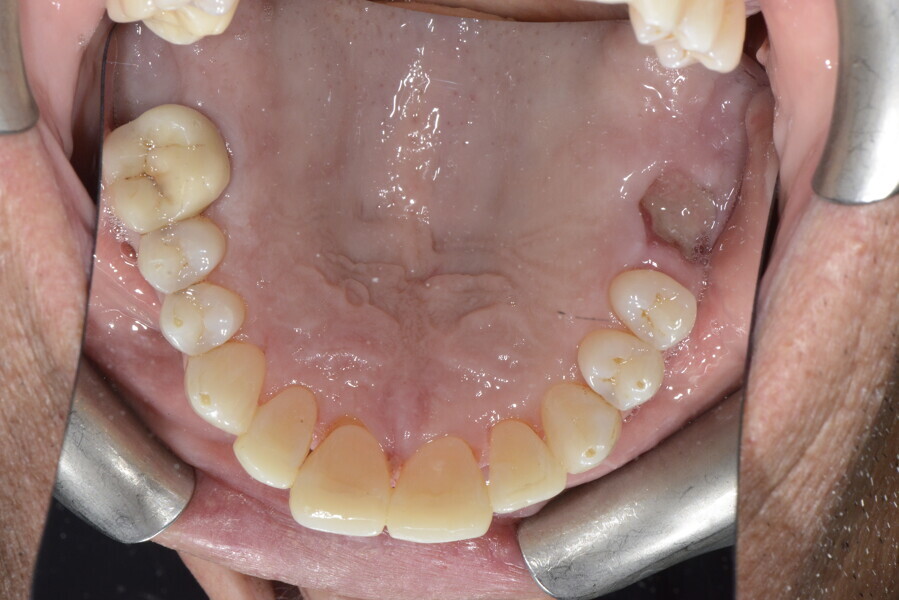

The 58-year-old patient wished to improve his oral aesthetics and function, complaining of mobility of the posterior teeth and wear of the anterior teeth. After data collection, a very complex situation was identified (Figs. 11–13):

1. severe periodontitis with poor prognosis of some teeth;

2. anterior crossbite;

3. severe wear mainly of the anterior teeth and compensatory eruption;38

4. atypical swallowing and lower posture of the tongue at rest;

5. masticatory dysfunction during the mastication test; and

6. no significant signs of temporomandibular disorder.